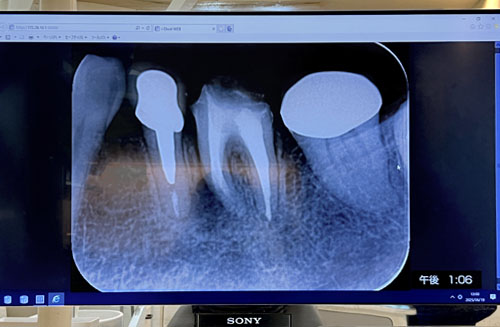

Final X-ray of the root canal

京橋・藤見歯科へ。

いよいよ第1大臼歯の Root Canal 治療の最終日。

一年かけてきれいに清掃したRoot(わたしの奥歯には4本のrootがあるという)を消毒して、最終の詰め物(根管充填材)をする。

奥の方は通常のゴムの詰め物(Gutta Percha Points:ガッタパーチャ)。手前の方のルートは骨が空洞になっているところがあるので、消毒効果のあるセメント(MTA-Fillapex?)を詰めたとのこと。

いつもは90分のセッションだが、今日はなんと120分。ずーっと口を開けていたので顎が疲れた。

これで銀座本院での治療は終了。このあとは、信濃町医院で上物(セラミックのキャップ)をつけるという手順。